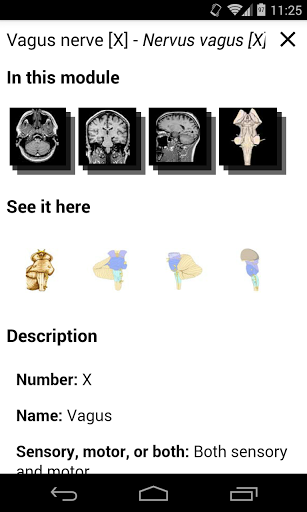

- Toque las etiquetas para mostrar las estructuras anatómicas

*Vista detallada mejorada de partes anatómicas para una identificación más fácil en imágenes del módulo actual y otros.

la vista de detalles de una estructura anatómica ahora se muestran los términos relacionados

-Dentro de la vista de detalles de una estructura anatómica , un alfiler ahora señala la estructura relacionada en todas las imágenes presentes

También toque directamente en la imagen para navegar a la imagen presentada en ese módulo